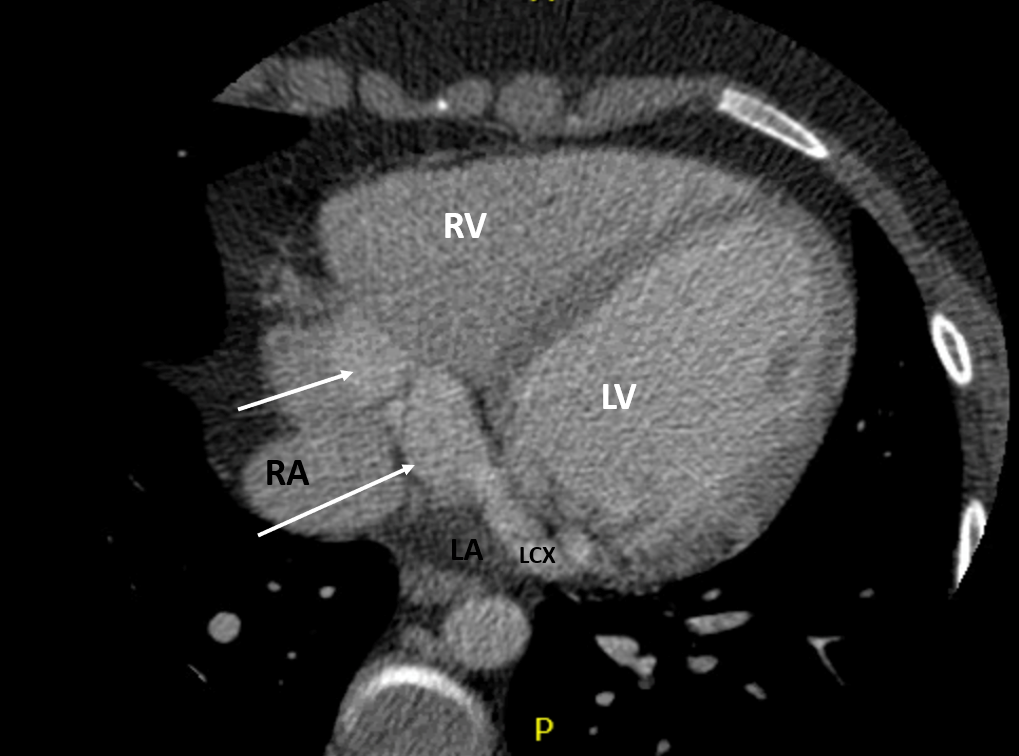

CT Heart

• Coronary artery fistula with features of macrofistulous communication of the distal left circumflex artery with the coronary sinus and presumed exophytic varix extending into the right atrium

• Circumflex measuring up to 9mm proximally and 26mm distally